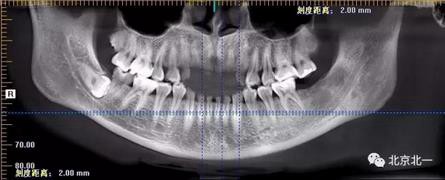

病例資料:一般情況,患者女性,28歲, 主訴:要求拔右側(cè)下頜智齒,檢查:右側(cè)下頜第三磨牙未見萌出, 拍片如圖。

圖一:CBCT顯示右側(cè)下頜水平骨埋伏牙,牙冠距離下牙槽神經(jīng)管接近。

圖二:自帶的CBCT顯示下牙槽神經(jīng)管貼著智齒走形。